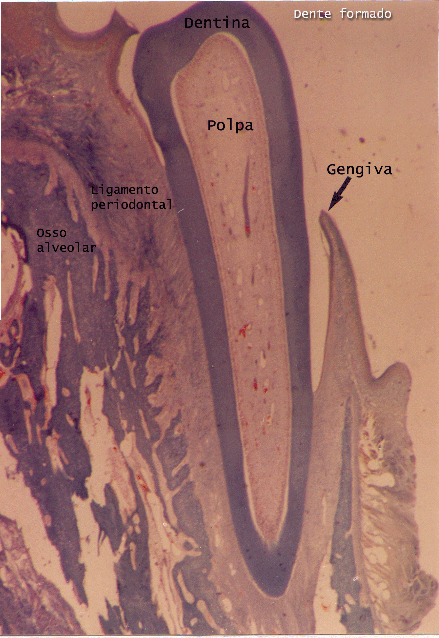

Desenvolvimento da face e odontogênese - Face and Tooth formation